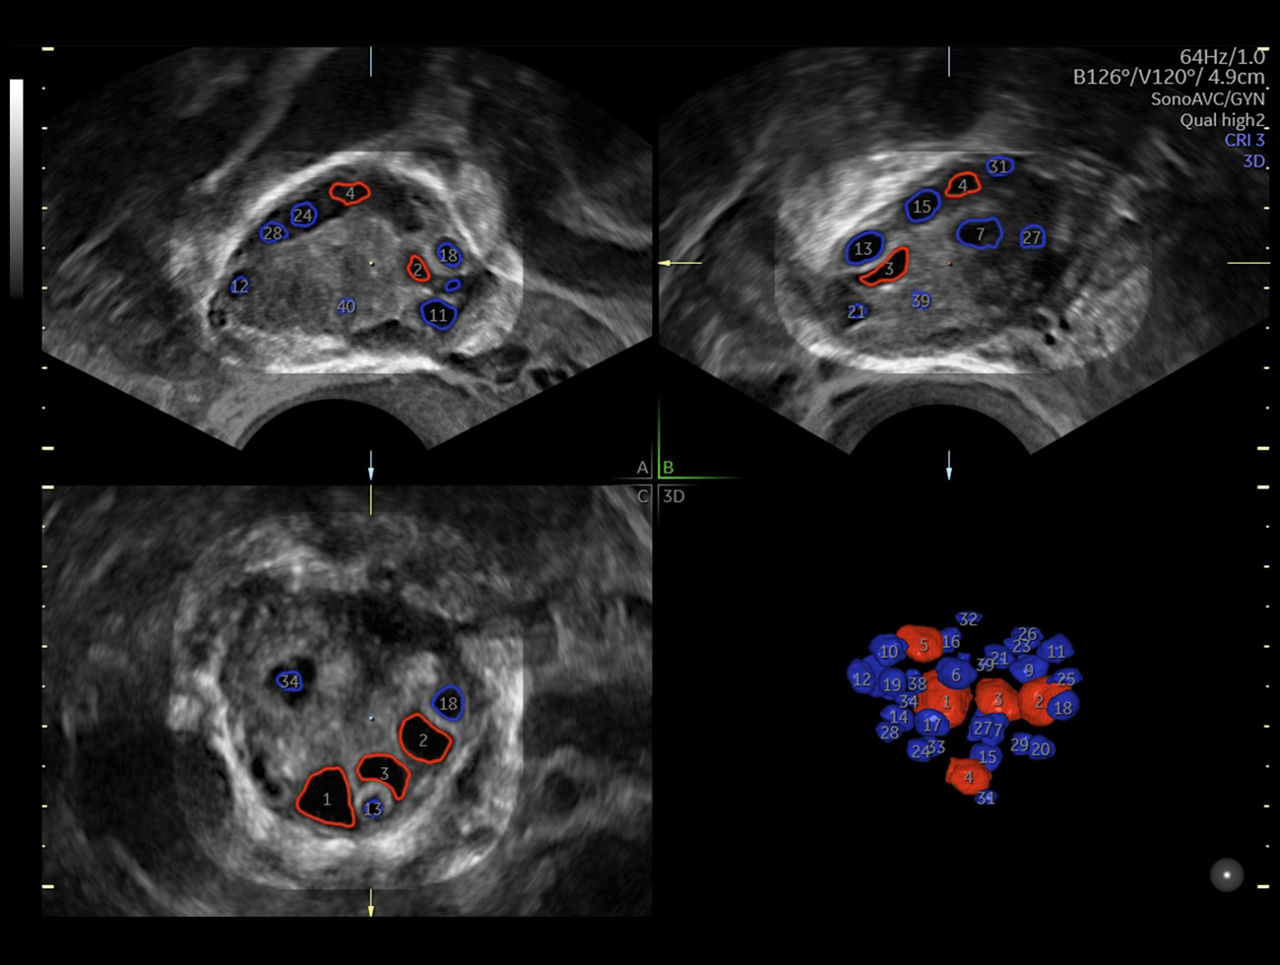

SonoAVC™follicle & SonoAVCantral

SonoAVC™follicle & SonoAVCantral automatically calculate the number, dimensions, and volume of hypoechoic structures for follicle monitoring or antral follicle count.